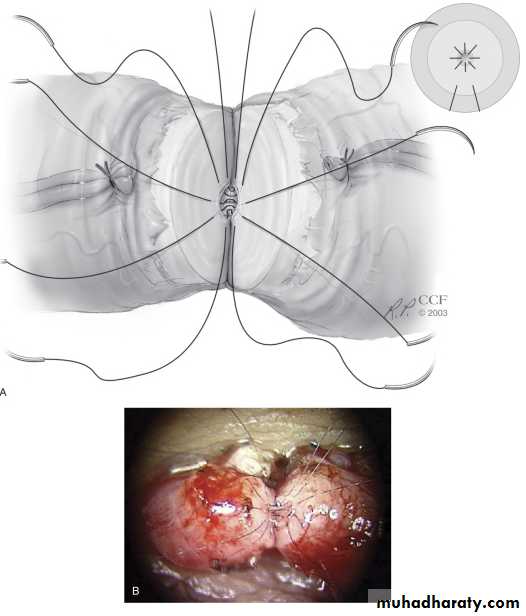

Vasovasostomy*indicated for vasectomy reversal.

*Complications

1.testicular atrophy 2. hematoma

3.recurrence(3-12%).

*patency & pregnancy rate:

Vaso-epididymostomy

indicated inreversal of vasectomy for >15 years(if vasovasostomy failed).

epididymal obsruction.

Patency rate: 30-65%.

Pregnancy rate: 20-40%.